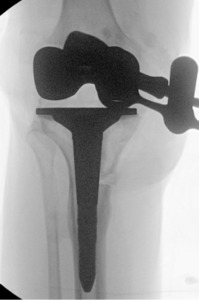

Pre-operative radiographs demonstrated Kellgren-Lawrence grade 4 tricompartmental osteoarthritis, 12° of tibial varus, a 22 mm deviation of the mechanical axis toward the medial side of the knee center, and an apex of angulation located 6 cm below the joint line (Figures 1 and 2). A follow-up computed tomography scan confirmed the absence of rotational malunion.

The two TTO cortical screws were removed. Attention then turned to the extra-articular deformity. Under biplanar fluoroscopic control an oblique medial open-wedge osteotomy was created six centimeters distal to the tibial plateau at the apex of the varus malunion (Figure 3). A laminar spreader was gently inserted and opened until a neutral mechanical hip–knee–ankle axis was achieved, as confirmed with an extramedullary alignment rod extending from the center of the femoral head to the center of the ankle mortise.

Trial components were inserted and demonstrated balanced flexion and extension gaps and central patellar tracking without the need for lateral release. The tibia was subsequently punched after confirming appropriate rotation for adequate patellar tracking. Final implantation proceeded with pressurized cement for the posterior-stabilized femoral component and the tibial baseplate under tourniquet insufflation. The diaphyseal press-fit stem was again confirmed to span the osteotomy by more than two cortical diameters under fluoroscopic guidance (Figure 4). Autogenous cancellous graft harvested from the femoral chamfer cuts was tightly packed into the osteotomy gap and along the medial cortex. The patella was resurfaced with a medialized polyethylene button.